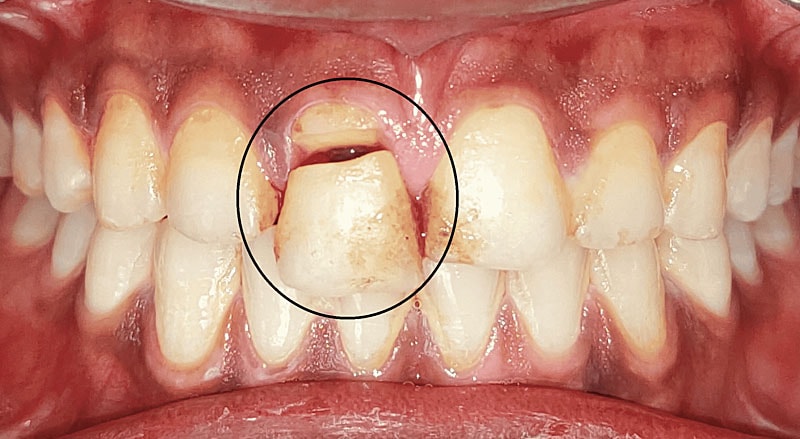

Fractura de diente urgente

Las fracturas dentales, causadas por traumatismos, resultan en dolor intenso y requieren atención inmediata para prevenir infecciones y pérdida dental. En caso de fractura, es crucial conservar el fragmento en leche o suero fisiológico hasta la consulta con el dentista.

Fracturas o Roturas Dentales

Causas

Traumatismos por caídas o impactos durante actividades recreativas.

Síntomas

Dolor inmediato, sensibilidad y dificultad para masticar.

Acción

Conservar el fragmento del diente en leche y acudir a la clínica para posible reimplantación o colocación de una corona temporal.